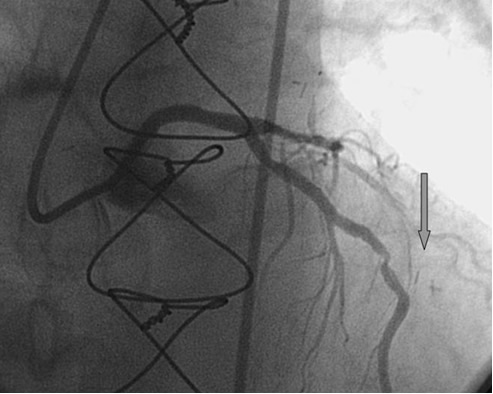

Ангиография при узелковом полиартериите: особенности исследования